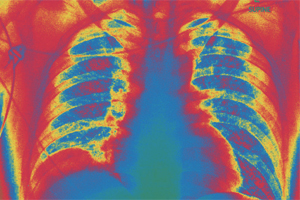

Respiration is a permanent process that never stops because the amount of air within our lungs must remain constant. This mechanism has specifically adapted organic structures: the respiratory pathways and the lungs.

Even though the structure of the lungs is conditioned to dilate and contract according to the entry or exit or air, the activity of other organs and tissues is needed to facilitate the respiratory process and they all work together.

The attached structures that collaborate in pulmonary ventilation are the diaphragm, intercostal muscles, thorax muscles and abdominal muscles. The entry of air and exit of carbon dioxide from our body is organized by mechanical respiration, which takes place in two stages: inhalation and exhalation. Both allow the air inside the lungs to be constantly replenished with fresh air.